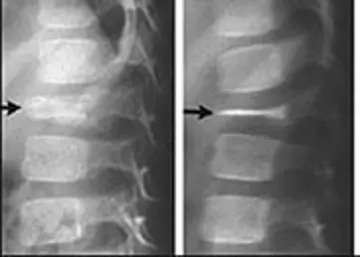

ترمیم خود‌به‌خود مهره مسطح

یک دختر3 ساله باسابقه‌ی سه هفته‌یی کمردرد مراجعه کرد.